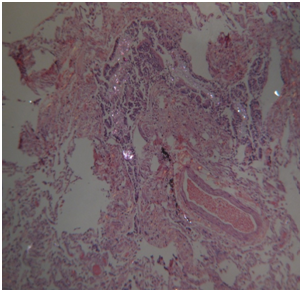

Histology: Acute emphysema was the prominent observation; edema and hemorrhages were also present.4 In 9 cases (Figures 3-6), exogenous material in the airways, comprehensive of planktonic boli in the lower branches, clearly demonstrable at polarization microscope (and possibly confirmable at SEM’s elemental analysis with EXD). Zoo- and phytoplankton have been better identified in the UV microscope. It is mandatory to differentiate the planktonic material from gastric content, regurgitated and aspirated (Figure 7 & 8).

Figures 3,4 Drowning in seawater. Images of endoalveolar zooplankton (protoconch of crustacean) (EE, 480 X, polarized light).

Figure 5 Drowning in freshwater; recovery corpse in the sea after 20 days. Endoalveolar phyto- and geoplankton (EE, 240X, polarized light).

Figure 6 Drowning in freshwater; recovery corpse after few hours. Geo- and phytoplankton in a lower bronchus (EE, 120X, polarized light).